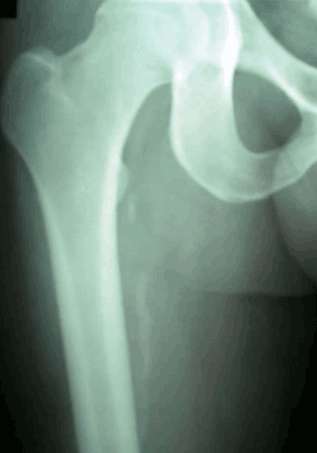

4.病理改变为肌肉和肌腱组织钙化沉积,治疗不当或者继续大负荷使用会最后导致肌肉骨化、断裂——这一点和伦纳德团队最近透风的内容很相似。下图大腿骨周围有些絮状阴影就是股四头肌沉积的钙质,大家可以想象下。